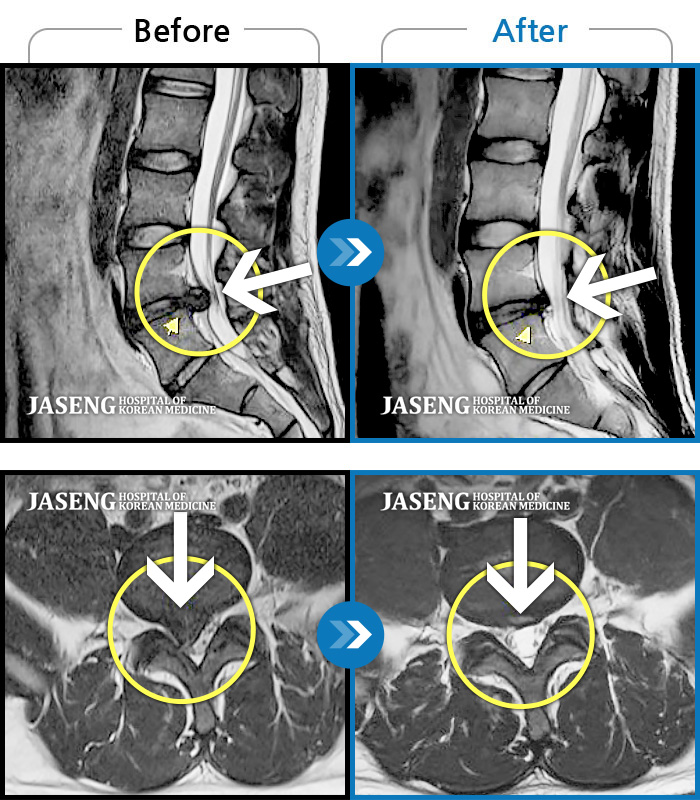

허리디스크

광주 · 이일석 원장

양측 허리부터 골반까지 묵직한 통증, 우측 다리 방사통이 심하여 내원하셨습니다.

촬영시기

2023.05.26 ~ 2025.08.16

2025.08.22